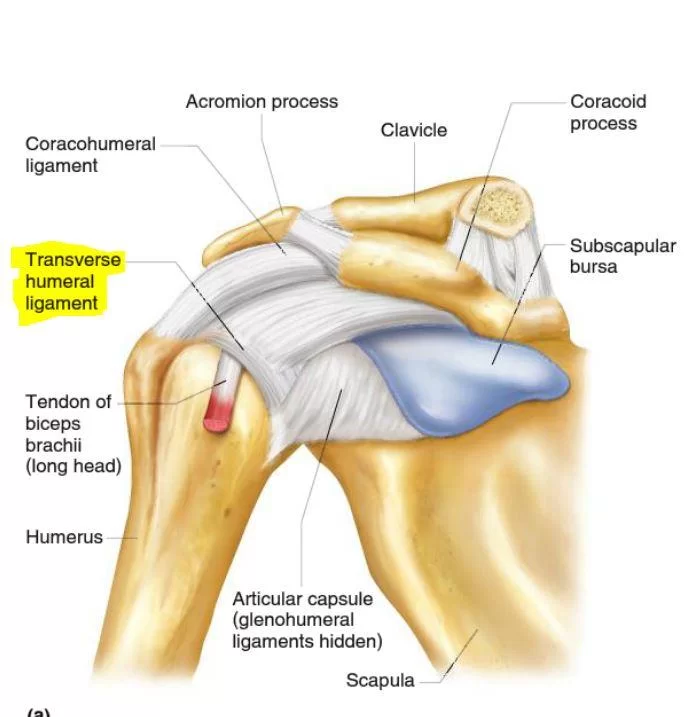

Glenohumeral ligament: анатомия и функции плечевого сустава